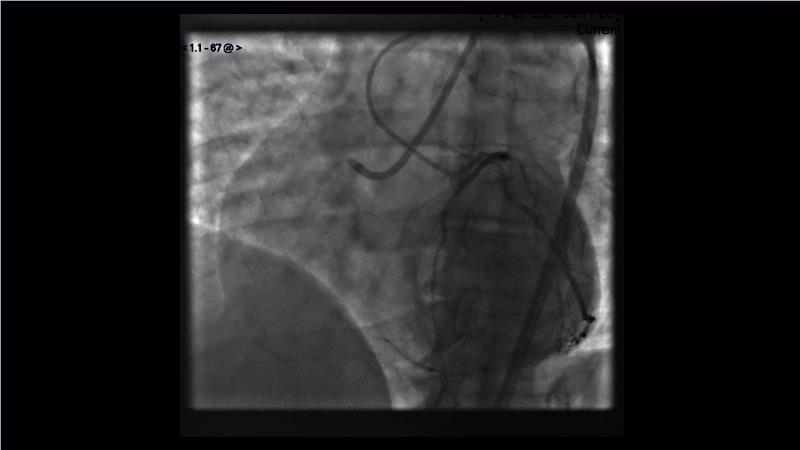

Watch this session to gain case-based insights on using DCBs in complex settings. Learn valuable tips and tricks for optimal DCB application, including the best timing and situations for their use. Discover how to effectively implement a hybrid strategy that combines DES and DCB when needed.

- To get a case based experience on how to use a DCB in complex settings

- To learn about tips and tricks on how and when to use a DCB: the ideal time and situation of DCB application in various complexities

- To utilise the hybrid strategy approach Combining DES and DCB when the situation demands